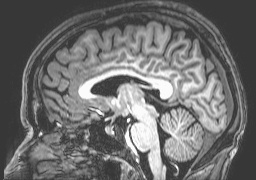

Is it possible to predict what a person is thinking of – or even what they are planning to do – based alone on their current brain activity? This project investigates ways to decode and predict a person’s thoughts from functional magnetic resonance imaging (fMRI) data. The key is that each thought is associated with a unique brain activation pattern that can be used as a signature or for that specific thought. If we train a classifier to recognize these characteristic signatures we can read out a person’s thoughts from their brain activity alone. Such “thought reading” can reveal how information is neurally encoded in the brain. The idea is that it is only possible to decode a thought if one knows the correct code. This research has many potential application, as for example in detection of deception, in the control of computers and artificial prostheses by brain activity, or even (more controversial) in market research.